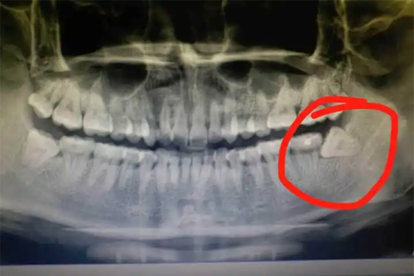

少数情况下可能出现持续疼痛或剧烈疼痛。若术后3天疼痛未减轻或伴随发热、脓性分泌物,可能提示干槽症或感染,需及时复诊处理。糖尿病患者或凝血功能障碍者术后疼痛恢复较慢,需加强创口护理。部分患者对疼痛敏感度较高,可提前与医生沟通镇痛方案。